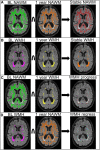

Methods and results: We defined areas of stable normal-appearing white matter, stable WMHs, progressing and regressing WMHs based on baseline and 1-year brain magnetic resonance imaging. In these areas we assessed tissue characteristics with quantitative T1, fractional anisotropy (FA), mean diffusivity (MD), and neurite orientation dispersion and density imaging (baseline only). We compared tissue signatures cross-sectionally between areas, and longitudinally within each area. WMH change masks were available for N=197. Participants' mean age was 65.61 years (SD, 11.10), 59% had a lacunar infarct, and 68% were men. FA and MD were available for N=195, quantitative T1 for N=182, and neurite orientation dispersion and density imaging for N=174. Cross-sectionally, all 4 tissue classes differed for FA, MD, T1, and Neurite Density Index. Longitudinally, in regressing WMHs, FA increased with little change in MD and T1 (difference estimate, 0.011 [95% CI, 0.006-0.017]; -0.002 [95% CI, -0.008 to 0.003] and -0.003 [95% CI, -0.009 to 0.004]); in progressing and stable WMHs, FA decreased (-0.022 [95% CI, -0.027 to -0.017] and -0.009 [95% CI, -0.011 to -0.006]), whereas MD and T1 increased (progressing WMHs, 0.057 [95% CI, 0.050-0.063], 0.058 [95% CI, 0.050 -0.066]; stable WMHs, 0.054 [95% CI, 0.045-0.063], 0.049 [95% CI, 0.039-0.058]); and in stable normal-appearing white matter, MD increased (0.004 [95% CI, 0.003-0.005]), whereas FA and T1 slightly decreased and increased (-0.002 [95% CI, -0.004 to -0.000] and 0.005 [95% CI, 0.001-0.009]).

Conclusions: Quantitative magnetic resonance imaging shows that WMHs that regress have less abnormal microstructure at baseline than stable WMHs and follow trajectories indicating tissue improvement compared with stable and progressing WMHs.